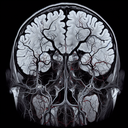

МРТ ангіографія діагностика судин голови та шиї

Магнітно-резонансна ангіографія (МРТ ангіографія) судин голови та шиї – це неінвазивний метод обстеження, який дозволяє оцінити стан кровоносних судин у зазначених областях. Процедура ефективна для виявлення аневризм, стенозу, тромбів та інших судинних патологій. Основні переваги МРТ ангіографії: 1...